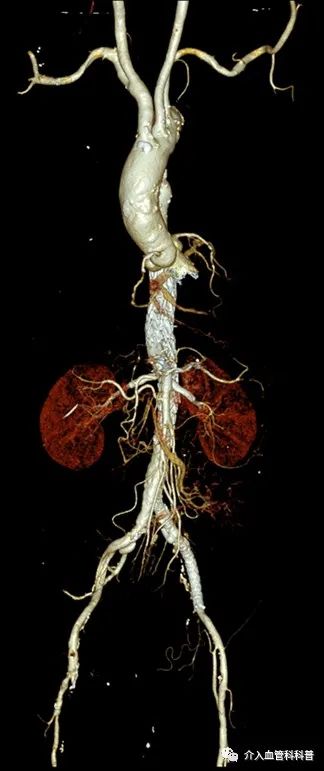

术后1年复查CTA提示支架位置良好,肠系膜上动脉及双肾动脉血流通畅,主动脉支架无内漏,无任何并发症。